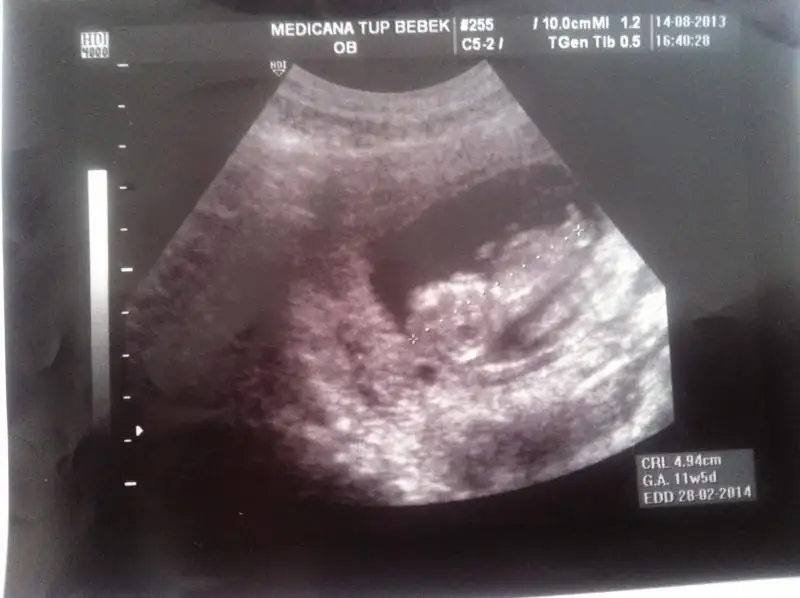

Merhabalar

buda benim bebeğimin ultrason görüntüsü

henüz 11 +3 haftalık resmine çıplak gözle bakınca popo kısmında bir çıkıntı görülüyor fakat resmi tarayıp yükledim ama pek bir şey anlaşılmıyor galiba

acaca görebildiğiniz kadar yorum yapabilir misiniz Eki Görüntüle 806765 Eki Görüntüle 806765

Dikkatli baktım canım sanin çıkıntın paralel KIZ .. Gönlündeki olsun